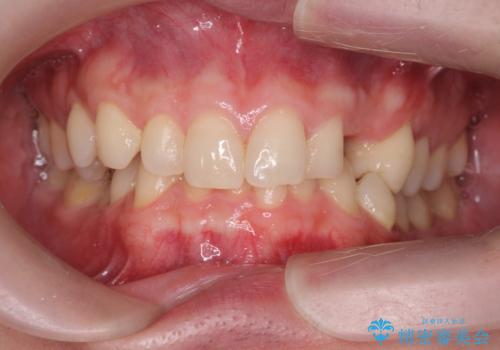

前歯に目立たないノンクラスプデンチャーを作りたい

- 目立つ前歯の欠損の状況を改善されたい、と希望され来院されました。

歯を削らず、インプラント治療でもない方法を希望されたのでバネの目立たないノンクラスプデンチャーを製作します。